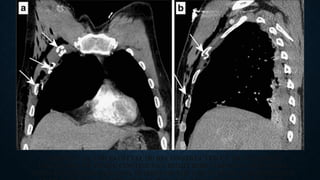

VASCULAR INJURY: SIGNS

• Signs of mediastinal hematoma

Widened mediastinum

Indistinct or abnormal aortic contour

Deviation of trachea or NGT to the right

Depression of left main bronchus

Widened paraspinal stripe

CT

Indirect signs of aortic injury:

Mediastinal hematoma

Periaortic fat stranding

CT Angiography:

100% sensitivity and specificity

Signs of mediastinal hematoma

Abnormal soft tissue density around mediastinal structures

Location – periaortic hematoma than isolated mediastinal hematoma remote from the

aorta.

SIGNS OF AORTIC

INJURY:

Intraluminal filling defect (intimal

flap or clot)

Abnormal aortic contour (mural

hematoma)

Pseudoaneurysm & extravasation

of contrast